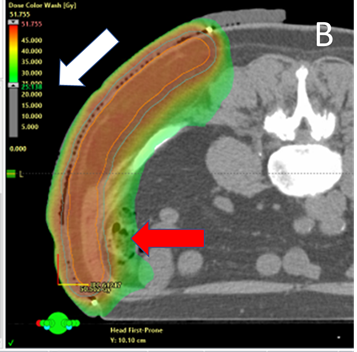

MV photons: MV photons penetrate more deeply that SXRT and electrons. The exit beam in deeper tissues beyond the target must be considered. Figure 4A details a case study where astute nursing helped predict and explain the acute reaction from MV photons.

A A 70-year old man with multiple recurrent melanoma arising within a large resection scar on the left flank required radical RT to control any future recurrence. Screen shot A shows the prone planning CT scan with an axial cut through the abdomen. The blue line is the PTV. The dose colour wash is set to 47.5Gy (white arrow) which is 95% of the prescribed dose of 50Gy. There is good coverage of the PTV. This plan was accepted by the RO.

B An astute nurse asked the planning team to provide a plan with the lower bar of the dose colour wash set to half the prescribed dose. Screen shot B shows the same axial cut as A but with the lower dose range set to 25Gy, or half the prescribed dose (white arrow). Note that some of the large colon (red arrow) is included in the volume getting this dose. The large colon is lined by gut epithelium, a hierarchically organised cell population. A possible side effect of treatment could be diarrhoea. The nurse was able to predict this and educate the patient as to why it may occur. The nurse could then pay particular attention to whether this symptom was starting and could quickly institute appropriate care if and when it happened to ensure timely course completion.

Figure 4 Predicting acute reactions from MV photons using the planning dose colour wash.